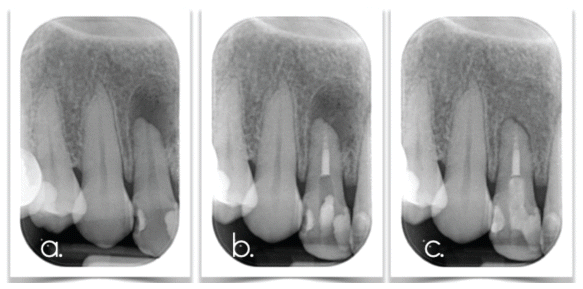

Regarding external apical resorption, in two-dimensional imaging, it appears as shortening and rounding of the apex with well-defined margins and the presence or absence of a periapical lesion, depending on whether an inflammatory cause is present. The root canal remains clearly visible and continuous. In three-dimensional imaging (CBCT), the authors describe asymmetry at the apex, conical loss of tooth structure, or a crater-like defect, with or without bone involvement, depending on the presence of an inflammatory etiology. When the cause is orthodontic treatment, multiple teeth are symmetrically affected.

It is caused by a microbial stimulus, namely, pulpal infection. The goal is to eliminate this microbial irritation. In permanent teeth with a closed apex, treatment includes endodontic therapy with chemomechanical preparation using sodium hypochlorite and EDTA, followed by placement of calcium hydroxide paste inside the canal for 2–3 weeks (14, 48, 50). Final root canal treatment is performed when radiographic signs of inflammation subside.

Therefore, the selection of the appropriate treatment must be based on differential diagnostic criteria that take into account: root maturity, pulp status, patient health and cooperation, and the clinician’s capabilities. In addition, several studies have examined pharmaceutical agents such as doxycycline, acetazolamide (58), ascorbic acid, and alendronate for the prevention or management of inflammatory resorption (59, 60, 61), but not for replacement resorption. Ledermix, which contains corticosteroids and antibiotics, has been shown to prevent inflammatory resorption, while Emdogain (62, 63) may contribute to periodontal healing, although its efficacy against ankylosis remains controversial. It should be noted that most of these studies involve replanted teeth and were conducted on animal models, limiting the generalizability of the results to humans (60, 62, 64). (Figures 2–4)

The term transient apical resorption also appears in the literature. This entity is observed in 23% of cases at 3 months and in 86% at 1 year after trauma. Radiographically, it appears as root shortening or blunting and is often misdiagnosed by clinicians as inflammatory resorption. In reality, it is an organismic healing process; therefore, periodic monitoring is recommended, especially if the patient exhibits no other symptoms. (Figure 5)